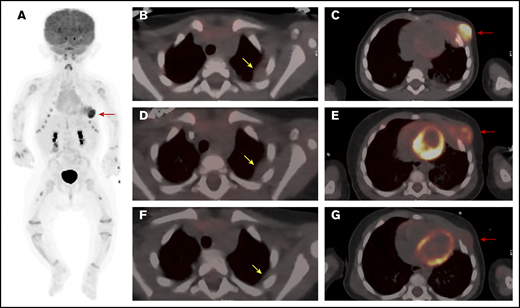

PET/CT scan of the chest at 3 time points. (A) Whole body anterior projection image from FDG PET/CT scan at diagnosis. Red arrow points to the FDG-avid left-sided chest wall mass. Sites of soft tissue uptake in both thighs represent injection sites from recent immunizations. Transverse fusion PET/CT sections through the thorax at baseline (B-C), following upfront standard therapy with vinblastine and steroids (D-E), and after therapy with dasatinib (F-G). At baseline, the mass extends into the subcutaneous fat of the left chest wall anteriorly and abuts the pericardium (C). The response to standard therapy was suboptimal with only mild reduction in size and FDG uptake (D-E). (G) Marked reduction in size as well as FDG avidity in response to dasatinib therapy. Yellow arrows point to sites of pleural thickening that were not FDG avid (1.4 × 1.8 cm). Note that the appearance of the pleural thickening did not change after standard therapy, but nearly resolved following dasatinib. Red arrows point at the large left-chest-wall mass centered at the left anterior fourth and fifth ribs and causing rib destruction.

A 4-month-old female infant presented with an enlarging mass lateral to the left nipple. Computed tomography (CT) scanning revealed a large left-chest-wall mass, measuring 5.0 × 2.9 × 2.6 cm, eroding the left fourth and fifth ribs and extending into subcutaneous fat (Figure 1A,C). Multiple areas of pleural thickening were noted over the left hemithorax, with the largest measuring 1.4 × 1.8 cm (Figure 1B). Left hilar and paracardiac lymphadenopathy was observed, with the largest lymph node measuring 0.8 × 0.9 cm. No pulmonary parenchymal lesions were noted. A staging positron emission tomography (PET) scan showed markedly increased uptake of fluorodeoxyglucose (FDG) in the left-chest-wall mass with areas of pleural thickening exhibiting only slightly increased metabolic activity. The PET-CT scan and a skeletal survey revealed no additional abnormalities. Initial laboratory studies, including a peripheral blood count and differential, were normal, and a bone marrow biopsy and aspirate showed normocellular marrow with balanced and orderly trilineage hematopoiesis.

Once the diagnosis was established, the patient began treatment with vinblastine (0.2 mg/kg IV weekly) and prednisolone (13.3 mg/m2 orally thrice daily). The chest wall mass showed a subjective decrease in size upon initiation of therapy but regrew quickly thereafter. After 6 weeks, the mass was unchanged in size from the initial presentation, with only a slight reduction in FDG avidity (Figure 1D-E). Due to the inadequate clinical response, therapy was changed to single-agent dasatinib (80 mg/m2 per day) based on tumor positivity for the MRC1-PDGFRB fusion, which is predicted to lead to activation of the PDGFRB. Several recent reports support the use of imatinib or dasatinib in the treatment of neoplasms harboring PDGFRB-activating mutations.9,10

Following initiation of dasatinib therapy, the patient showed a steady and dramatic clinical response with a reduction in the size of the primary tumor. After 5 months of targeted therapy, PET-CT scanning showed a marked reduction in the size and activity of the primary tumor and near complete resolution of the pleural mass (Figure 1F-G). After 9 months of therapy, physical examination demonstrated continued improvement with the palpable mass measuring ∼1 cm in size.